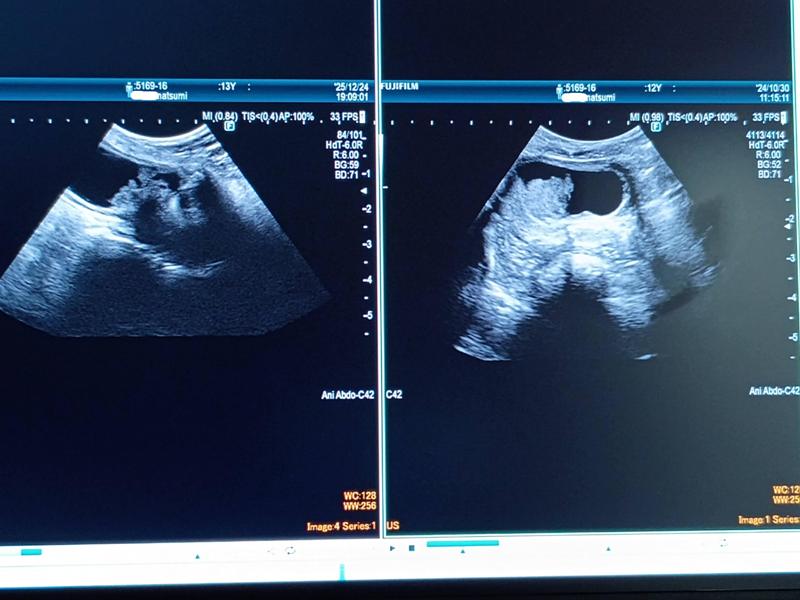

2025年の年末、腫瘍の状態や転移の有無を確認するために約1年ぶりに超音波検査を受けました。

左が2025年12月、右が2024年10月の状態です。

膀胱内の尿量の関係で、画像の比較では対応する部分がわかりづらいのですが、動く映像で確認された先生からの説明では、

「腫瘍は高さ方向へはそれほど拡大していないが、横方向への広がりは多少見てとれる」

「昨年は明瞭だった膀胱壁との境目がぼやけており浸潤が進んでいる」「他の臓器やリンパ節への転移は見られない」

とのこと。

14か月間での進行度合いとしては顕著なものではなく、一定程度の治療効果があったようだという所見でした。素人目にも尿が通れる空間がまだ残っていることを確認できたので、少し安心することができました。